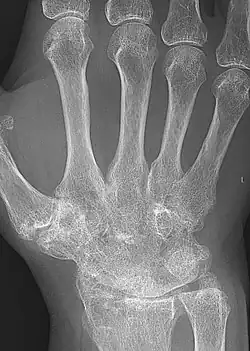

X-rays of the hands and feet are generally performed when many joints are affected. In RA, there may be no changes in the early stages of the disease, or the X-ray may show osteopenia near the joint, soft tissue swelling, and a smaller than normal joint space. As the disease advances, there may be bony erosions and subluxation. Other medical imaging techniques such as magnetic resonance imaging (MRI) and ultrasound are also used in RA.[20][79]

Technical advances in ultrasonography, like high-frequency transducers (10 MHz or higher), have improved the spatial resolution of ultrasound images, depicting 20% more erosions than conventional radiography. Color Doppler and power Doppler ultrasound are useful in assessing the degree of synovial inflammation as they can show vascular signals of active synovitis. This is important since in the early stages of RA, the synovium is primarily affected, and synovitis seems to be the best predictive marker of future joint damage.[80]